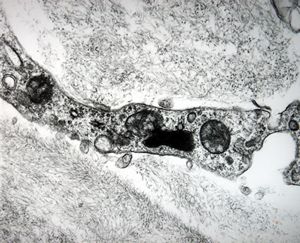

jejunumblood capillarz in lamina propria

venule in lamina propria